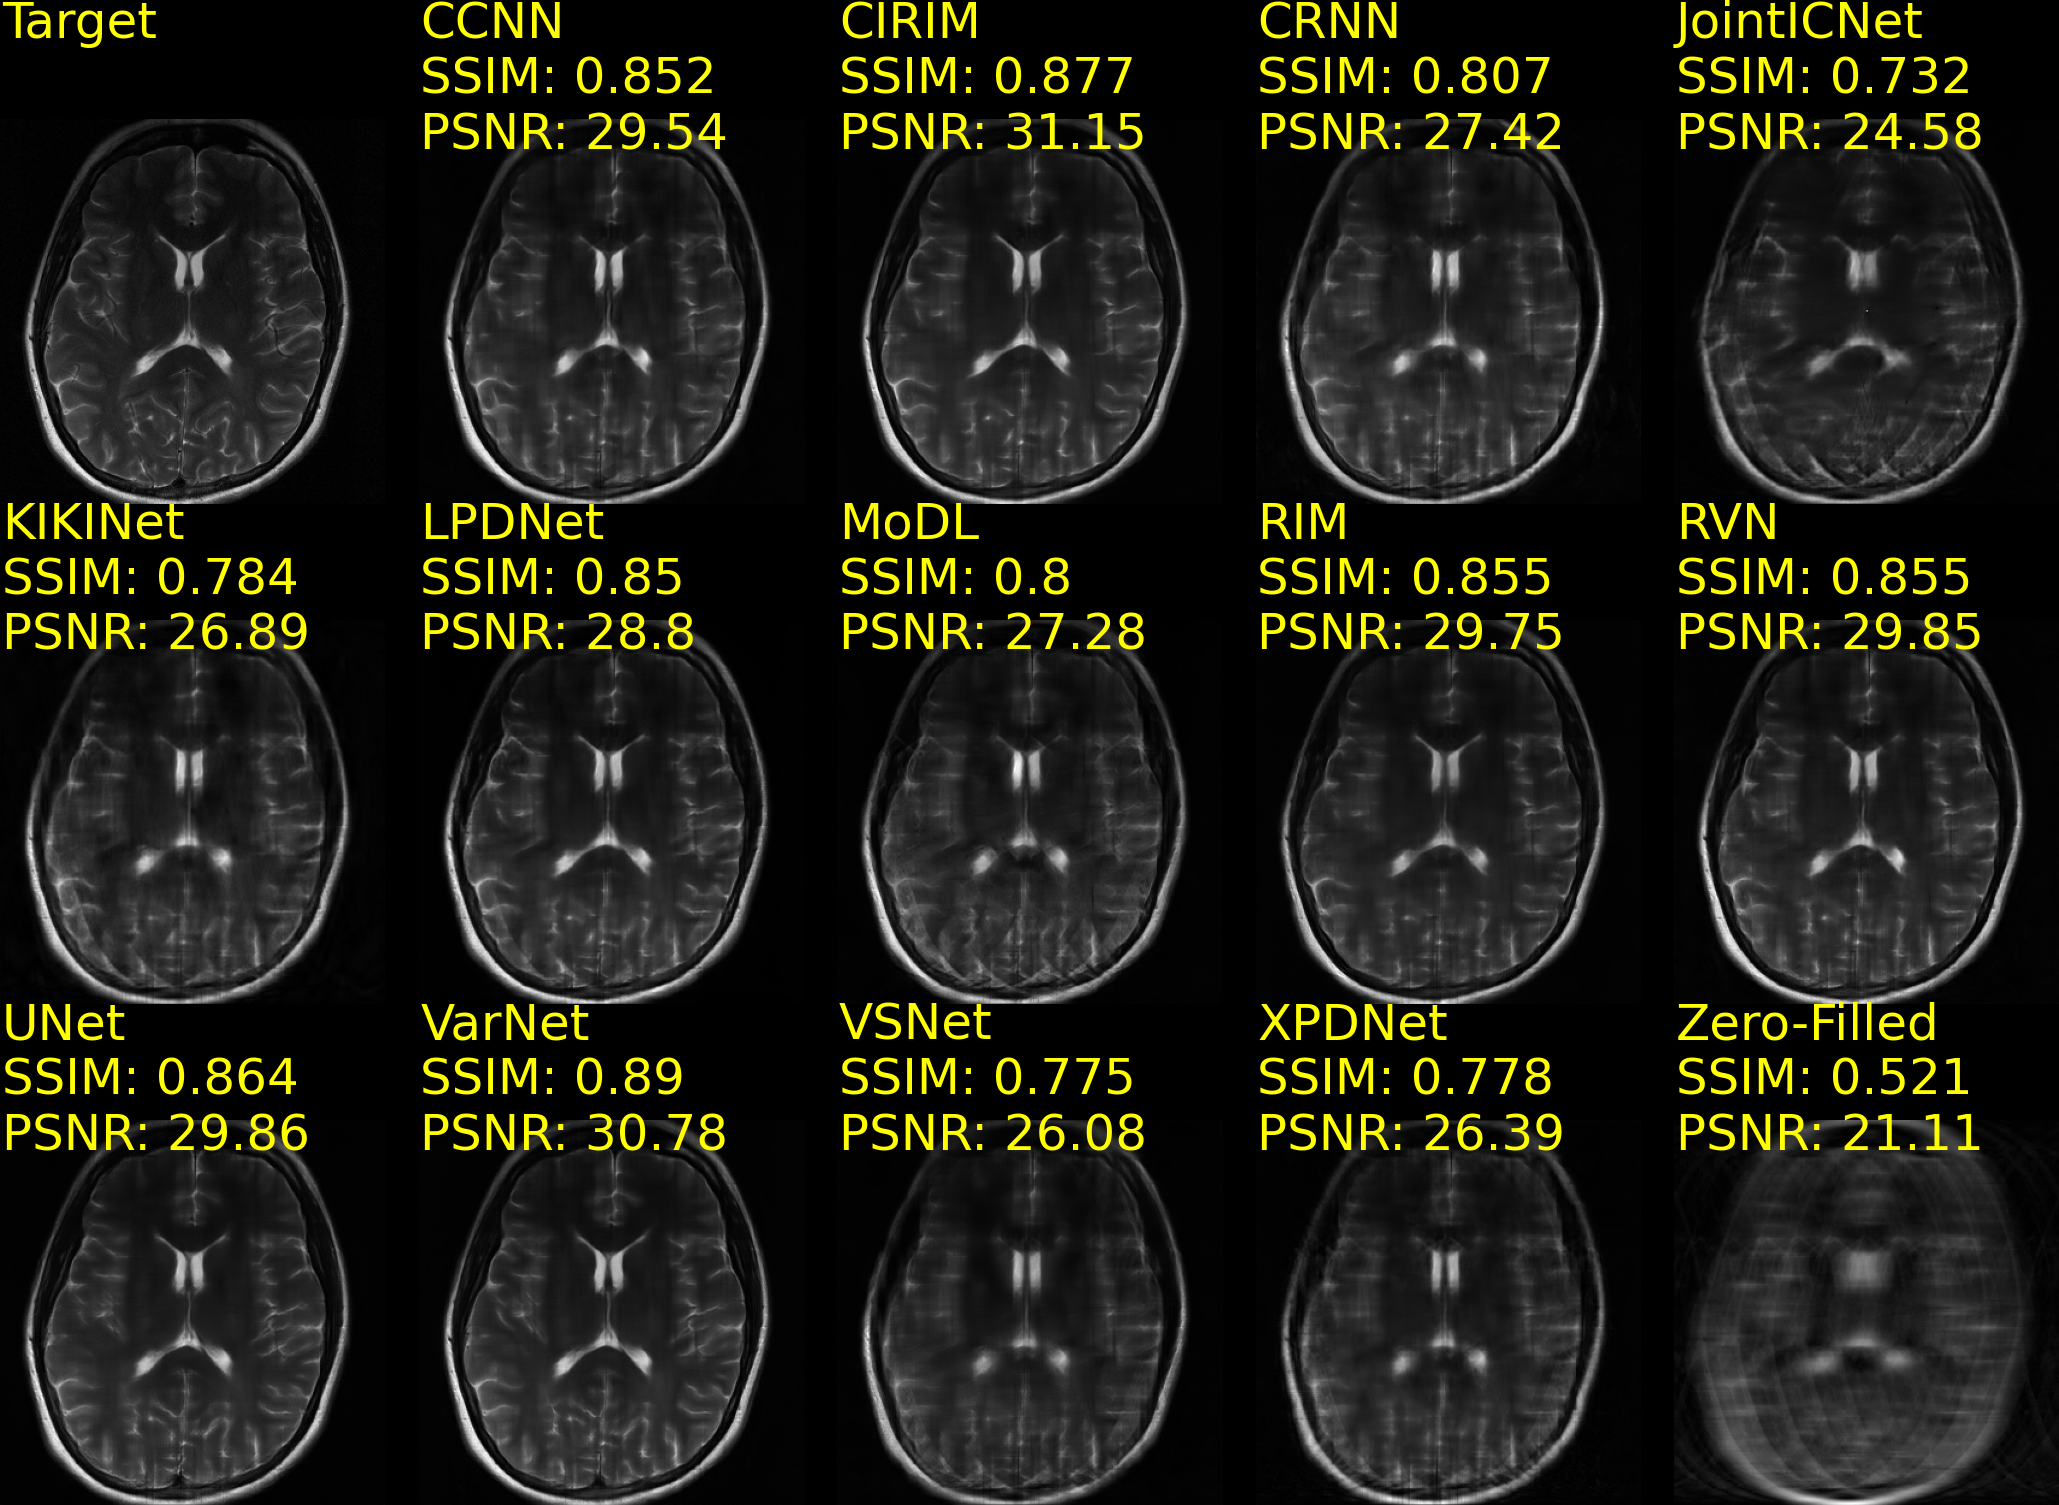

Example reconstructions of brain data are shown in Fig. 5(a) and Fig. 5(b), from the CC359 dataset, and Fig. 6(a) and Fig. 6(b), from the fastMRIBrain dataset. Figure 7 shows example reconstructions of knee data from the StanfordKnee dataset.

(a) fastMRIBrains 14-coil data - 4x acceleration

Refer to caption

(b) fastMRIBrains 14-coil data - 8x acceleration

Figure 6: Reconstructions of 14-coil T2-weighted data from the fastMRI Brains dataset, undersampled with an Equispaced 1D sampling pattern for 4x (Fig. 6(a)) and 8x (Fig. 6(b)) acceleration. The top row-first column shows the ground truth (Target) image. SSIM and PSNR scores are reported for each method and computed against the Target image. Methods are sorted alphabetically.